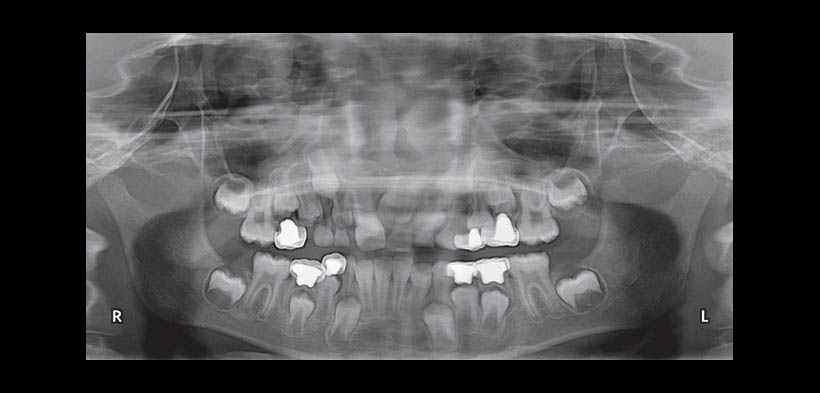

Fig. 3. Radiografía panorámica: Seis meses postoperatoria mostrando reabsorción completa del material de obturación de las zonas periapicales.

Fig. 4. Radiografía panorámica: 12 meses postoperatorios mostrando reabsorción del material de obturación junto con la reabsorción radicular en las piezas 8.4, 8.5, 7.4, 7.5 y 6.4.

Fig. 5. Radiografía panorámica: 30 meses postoperatorios mostrando reabsorción radicular completa en todos los dientes excepto de las raíces distales de las piezas 7.5 y 8.5.